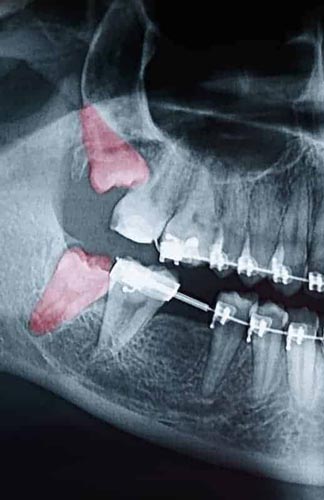

La mayoría de las personas tienen espacio suficiente en la boca para 28 dientes. Cuando las muelas del juicio comienzan a salir, son cuatro dientes adicionales que intentan abrirse paso. En la mayoría de los casos, esto crea problemas, que incluyen apiñamiento, dolor, riesgo de infección y la necesidad de extracción. Dado que las muelas del juicio son las últimas en salir a través de las encías, llegan un poco tarde. Todos los demás dientes ya se han asentado en sus lugares. Con radiografías e inspecciones, podemos determinar si las muelas del juicio están impactadas y deben extraerse. Dado que las muelas del juicio rara vez salen derechas y alineadas con el resto de la sonrisa, en High Plains Oral & Facial Surgeons tenemos años de experiencia analizándolas y extrayéndolas. Las muelas del juicio también pueden salir de lado, lo que le puede causar aún más problemas si no actuamos. Si usted o su hijo se acercan a los 18 años, es fundamental que los lleve a un examen para ver si tienen muelas del juicio. Llámenos hoy para programar su cita para un análisis o extracción de muelas del juicio en Texas y el Suroeste.

Aunque algunos pacientes no necesiten la extracción de las muelas del juicio, la mayoría de las veces es necesaria para proteger la salud bucal en general. Las muelas del juicio pueden empezar a crecer de lado, erupcionar solo parcialmente o incluso quedarse atascadas debajo de la encía y el hueso. Las muelas del juicio, conocidas como dientes impactados, pueden recurrir a cambiar de posición mientras intentan encontrar una vía para la erupción. Cuando las muelas del juicio no erupcionan a través de la encía correctamente, pueden crear problemas graves para el paciente, entre ellos:

Para evaluar el estado de sus muelas del juicio, primero haremos un examen minucioso y tomaremos radiografías de su boca. Esto nos ayudará a determinar si sus muelas del juicio representan una amenaza actual o futura para su salud bucal. La detección temprana de problemas da como resultado mejores resultados para nuestros pacientes, por lo que recomendamos que la primera evaluación se realice a mediados de la adolescencia del paciente.